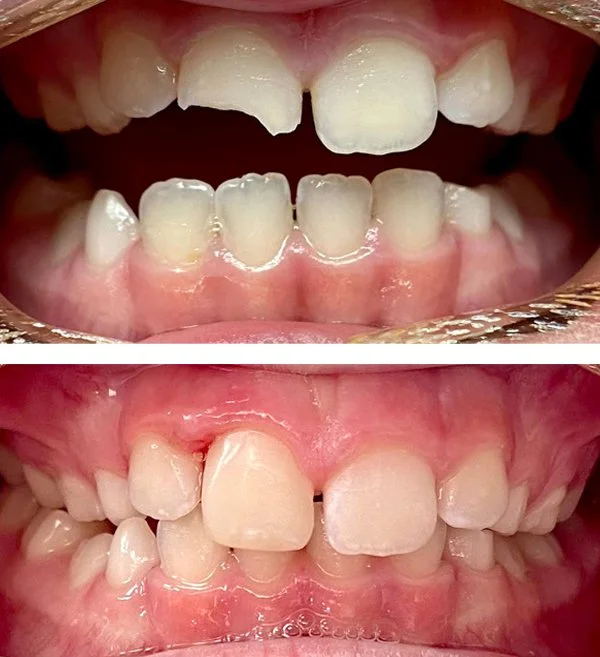

Emergencies

Relief from pain is the primary objective. Temporary and long term solutions available based on the clinical scenario.

Tooth Fracture